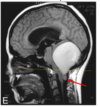

identify

tonsilar herniation (inf to foramen magnum)

d/t chiari I malformation

identify

tonsillar herniation (inf to foramen magnum)

d/t posterior fossa tumor